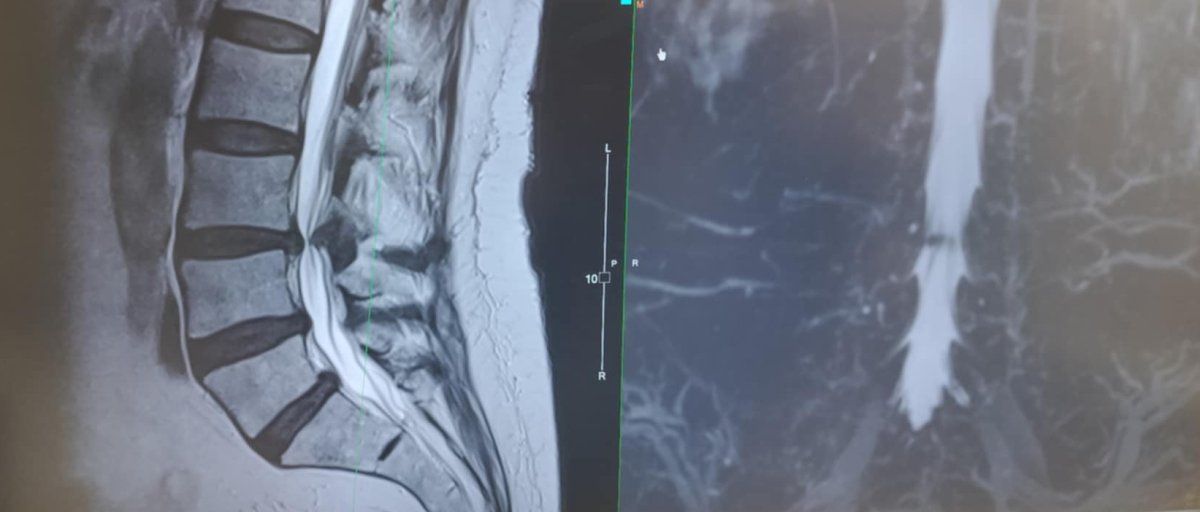

I've had X-rays and an MRI scan done and have been diagnosed with severe spinal stenosis. In Bangkok Hospital Pattaya they tried physio and a cortisone shot but they were no help at all. Surgery was recommended but I wasn't comfortable with the doctor I was seeing here, so I went to see Prof. Wicharn at BNH in Bangkok last week.

MRI scan back problem.jpg

With all due respect the MRI shows a clear but not severe stenosis. I have experience with 7000+ spinal procedures and that has taught me that the "size" of the operation poorly correlates with the speed of post-operative recovery. I have seen the young woman with the mini-surgery taking more time than the construction worker with a multi-level procedure. It is however important not to underestimate spinal surgery. All in all it requires about 2-6 weeks of gradual increase of activities, avoiding too much bending and lifting. A good alternation between resting and light activities works best. But in general the speed and level of recovery is highly individual and depends on other factors than just the extent of surgery.